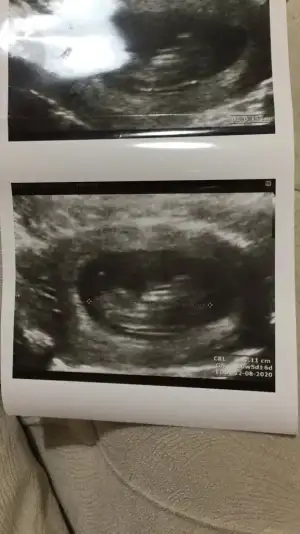

Sevgili İkra,

Yorumlarsan çok sevinirim. ☺️❤️